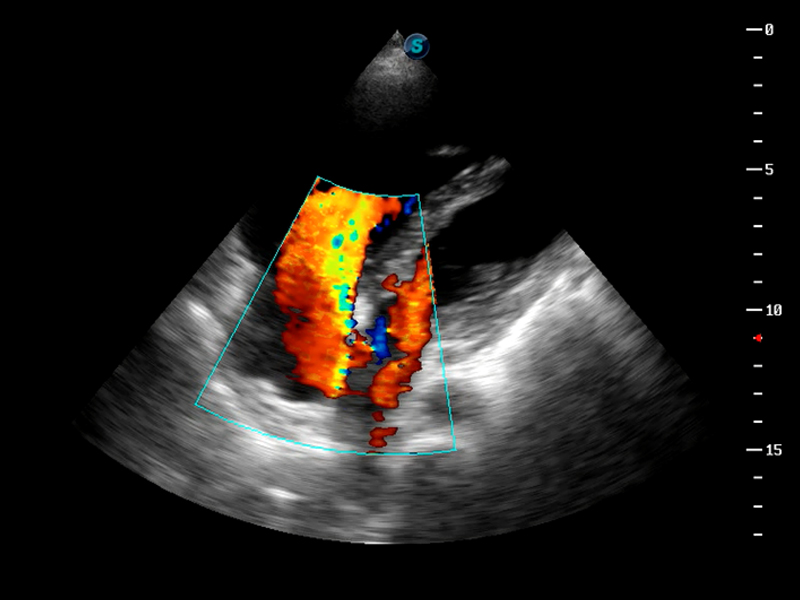

S9便携式彩色多普勒超声诊断仪是竞技宝(JJB)官方网站研发的高端便携彩超设备,外观设计新颖、产品性能卓越。S9在便携超声领域采用了突破传统的触摸屏交互设计,并以先进的软件硬件技术和设计理念,为您带来清晰的图像质量、稳定的工作性能和便捷的操作体验。

AutoC智能血流追踪